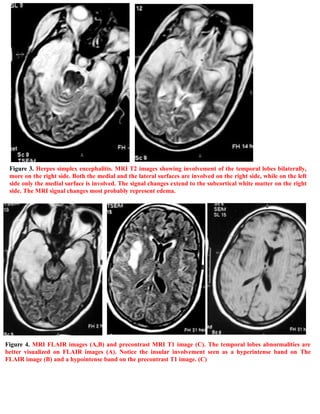

A 40-year-old female patient presented with fever, seizures, impaired consciousness, and signs of meningeal irritation. She was diagnosed with herpes simplex encephalitis. The document includes 6 figures showing MRI images of the brain that demonstrate abnormalities in the temporal lobes consistent with herpes simplex encephalitis. An addendum provides information on accessing updated versions and related publications on the editor's website.